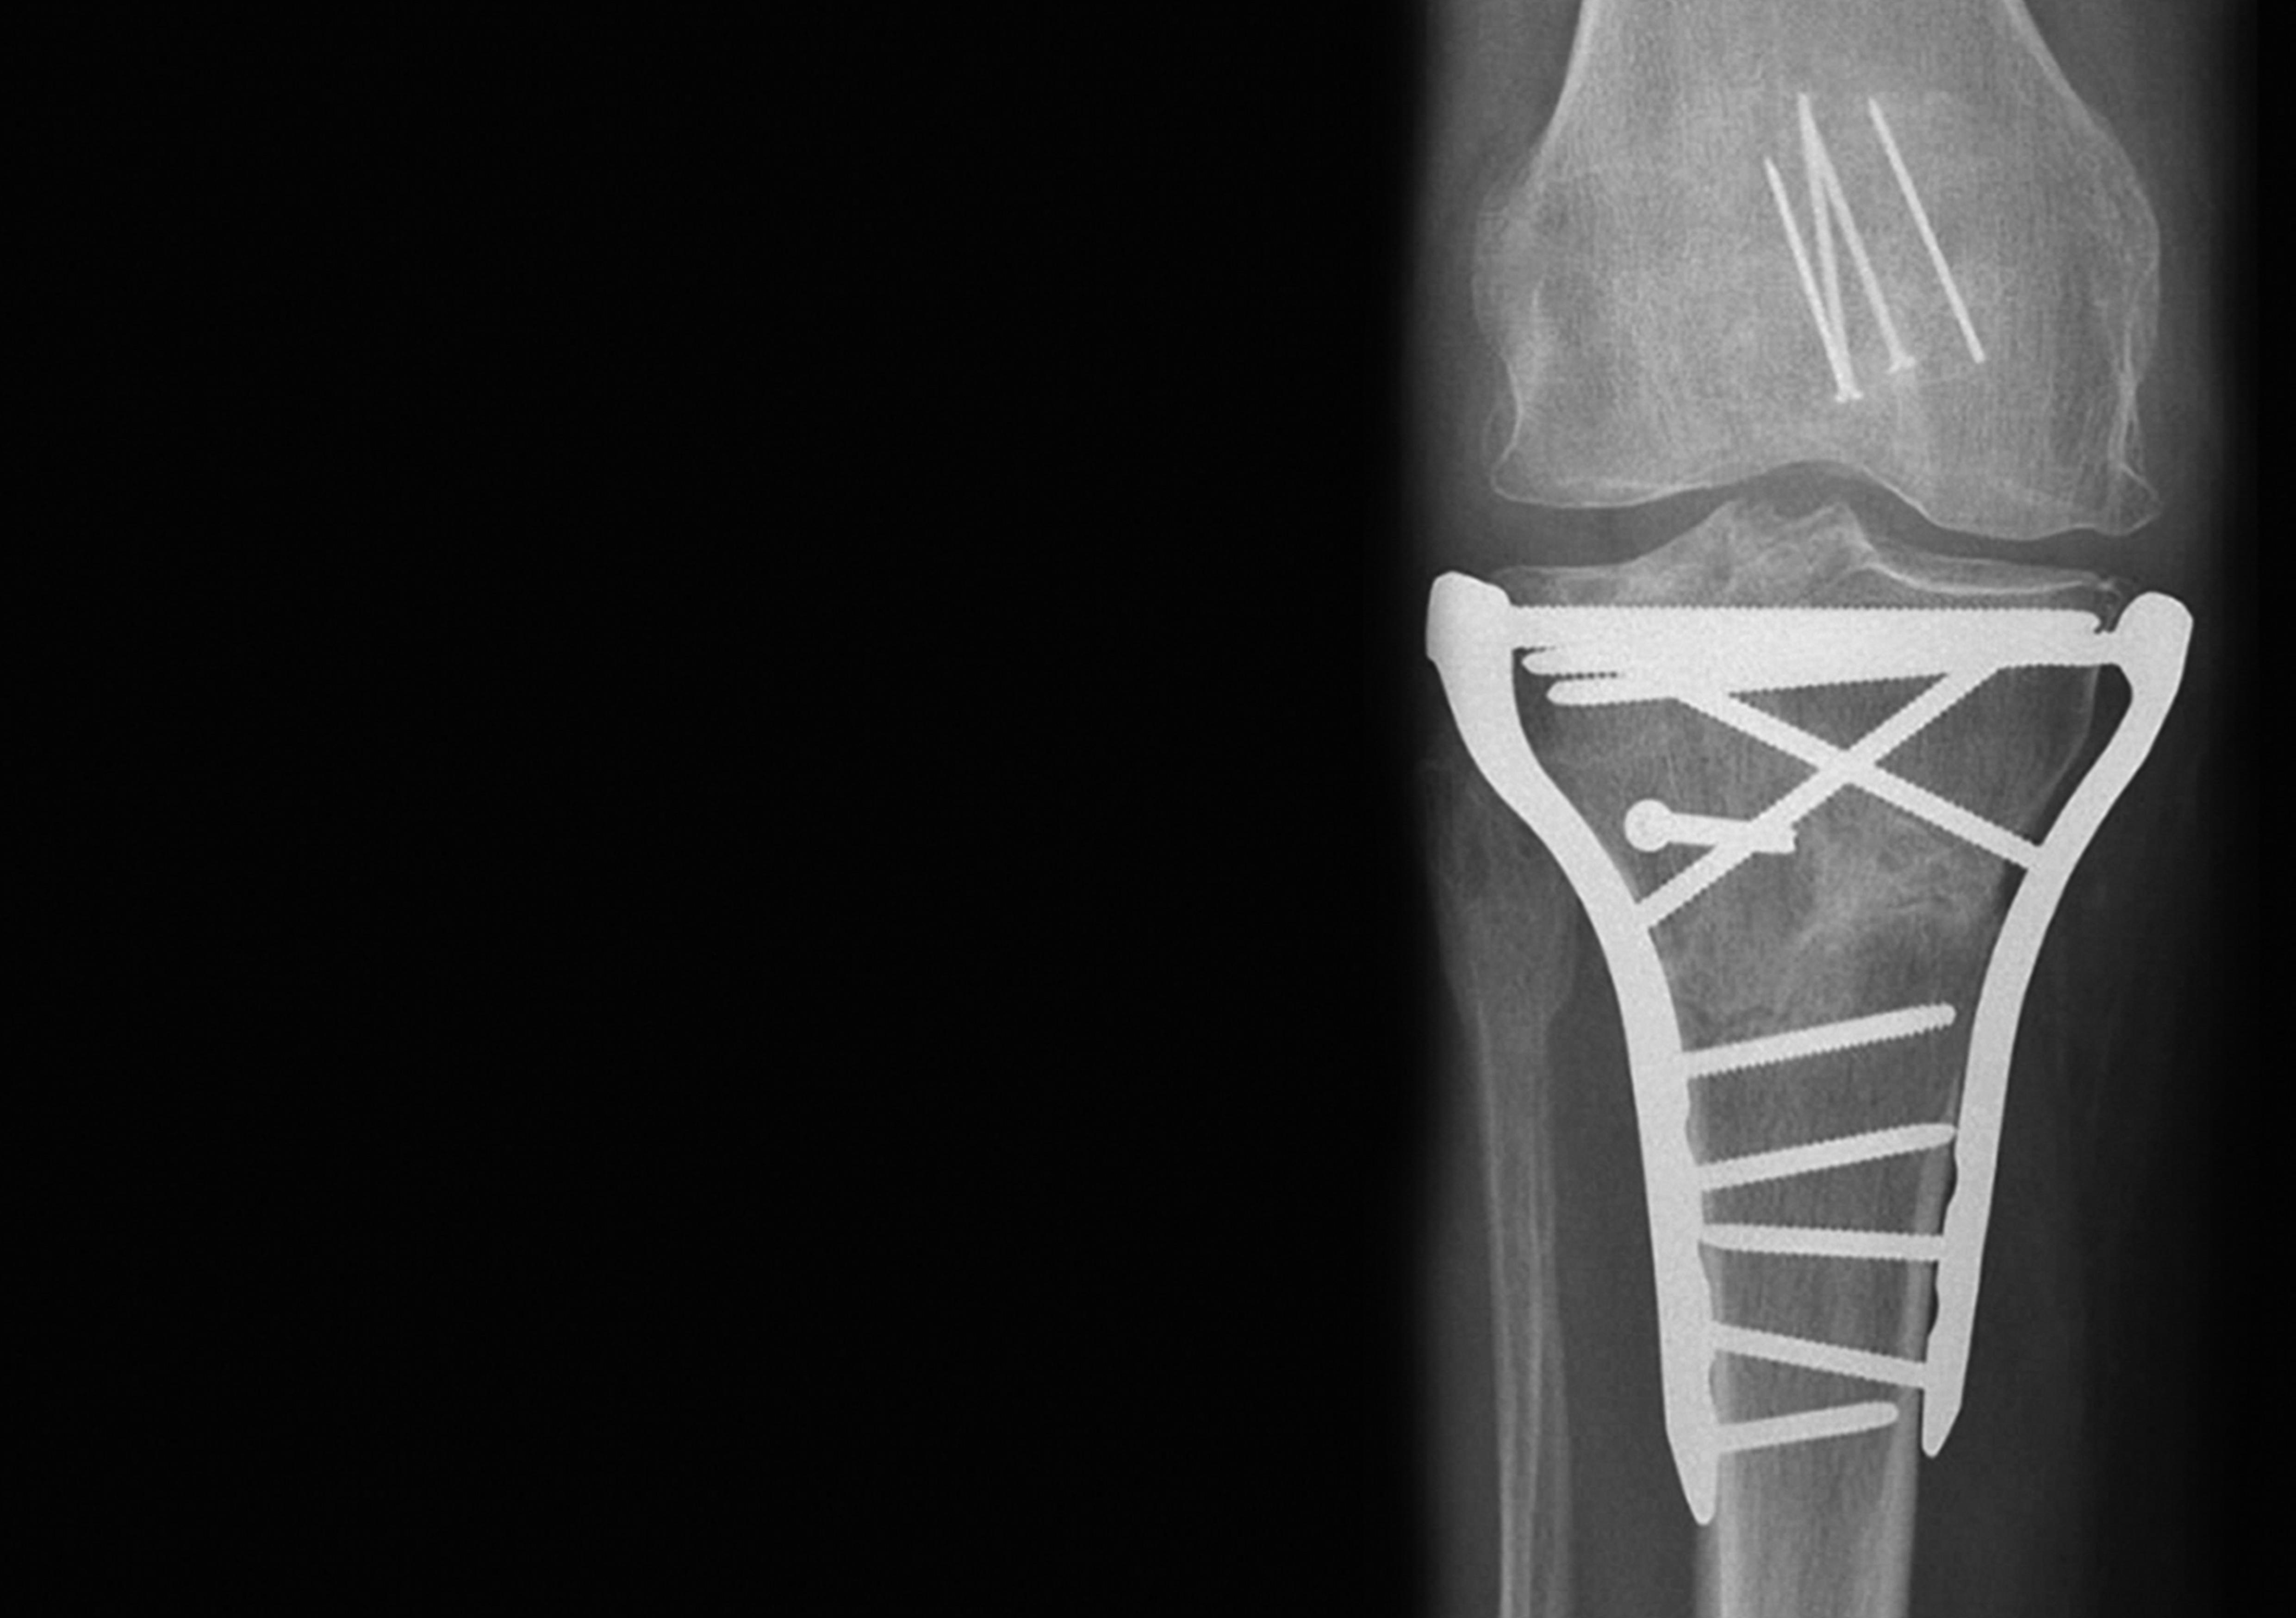

POYA CASE: COMPLEX FRACTURE OF THE RIGHT PROXIMAL TIBIA

A 60-year-old female patient sustained an isolated fracture of the right proximal tibia in a skiing accident.

Complex fracture of the right proximal tibia